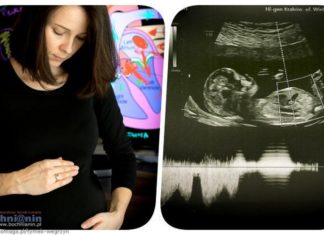

Nienarodzony Tymek z wadą serca potrzebuje pomocy

Tymek jeszcze się nie urodził, ale zdiagnozowano u niego wadę serca wymagającą skomplikowanego leczenia zaraz po urodzeniu. Rodzice chcą zapewnić mu możliwie najlepszą opiekę....